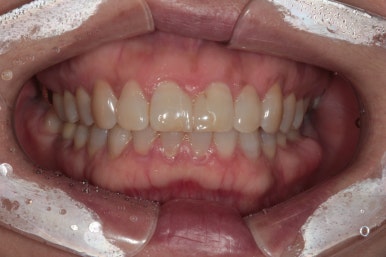

정면에서 본 사진입니다.

잘 모르실 수도 있겠지만, 잇몸이 염증이 생겨 치주염으로 인해 빨갛게 변하신 것을 보실 수 있어요.

즉, 잇몸질환-만성치주염을 갖고 계신 상태였죠.

위 앞니 (중절치)는 치아 사이 틈을 메우기 위해 예전에 레진치료를 받으신 상태였는데, 치료받으신지 오래되어 레진 충전물의 색이 변하고 어색한 모양을 띄고 있습니다.

앞면, 양쪽 옆면 모두 아주 깔끔하게 유지되고 있네요!

기억하고 있으실지 모르겠지만, 전반적으로 나타내고 있던 잇몸의 붉은색도 대부분 사라져 있는 상태입니다.

임플란트 또한 적절히 유지되고 있고 잘 사용하고 계신 상태입니다.

신경치료와 지르코니아 크라운 치료를 받았던 치아도 뿌리끝 염증 없이 잘 사용중이시구요!